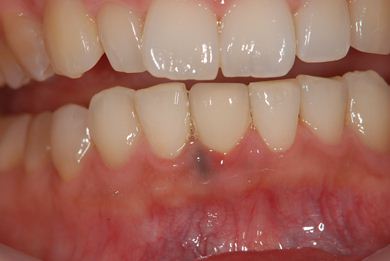

主訴 歯の差し歯が少しぐらつく。歯ぐきが違和感を感じる。

治療方針 抜歯と同時にインプラントを埋入し、治療期間を短縮する。

治療内容 インプラント1本(抜歯即日スピードインプラント)、メタルボンドセラミック1本

治療前